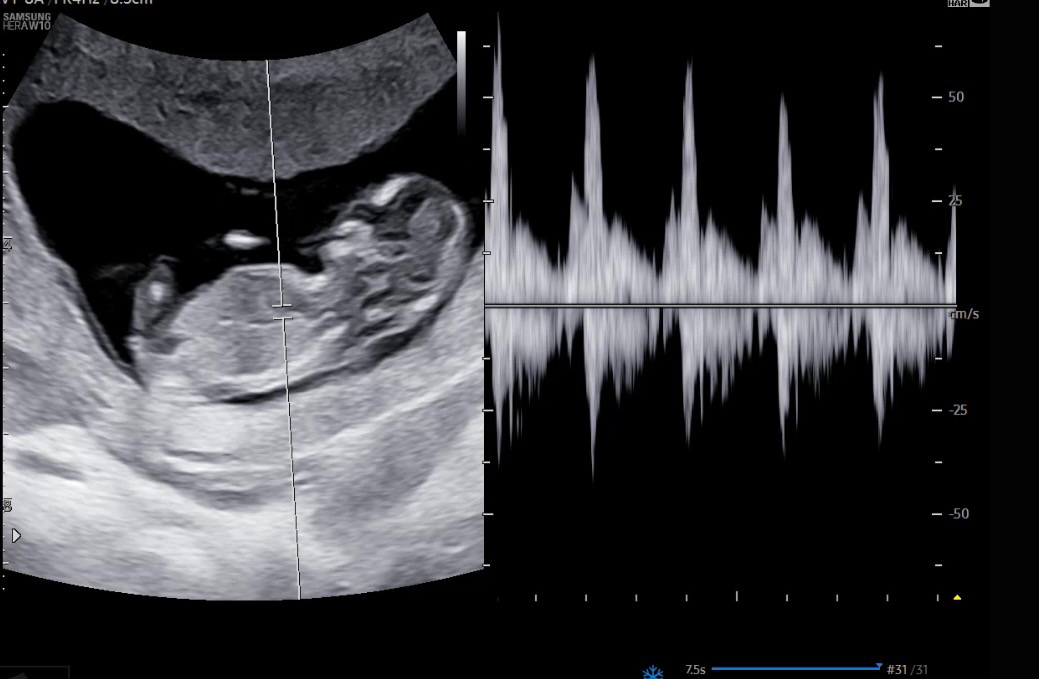

12주 각도법으로 딸일까요..?

딸인듯한데.. 어떠셔요?😶😶

끝갈라짐과 척추랑 평행인걸로봐서는 딸 같아요 ㅎㅎ

이사진에선 잘안보여용